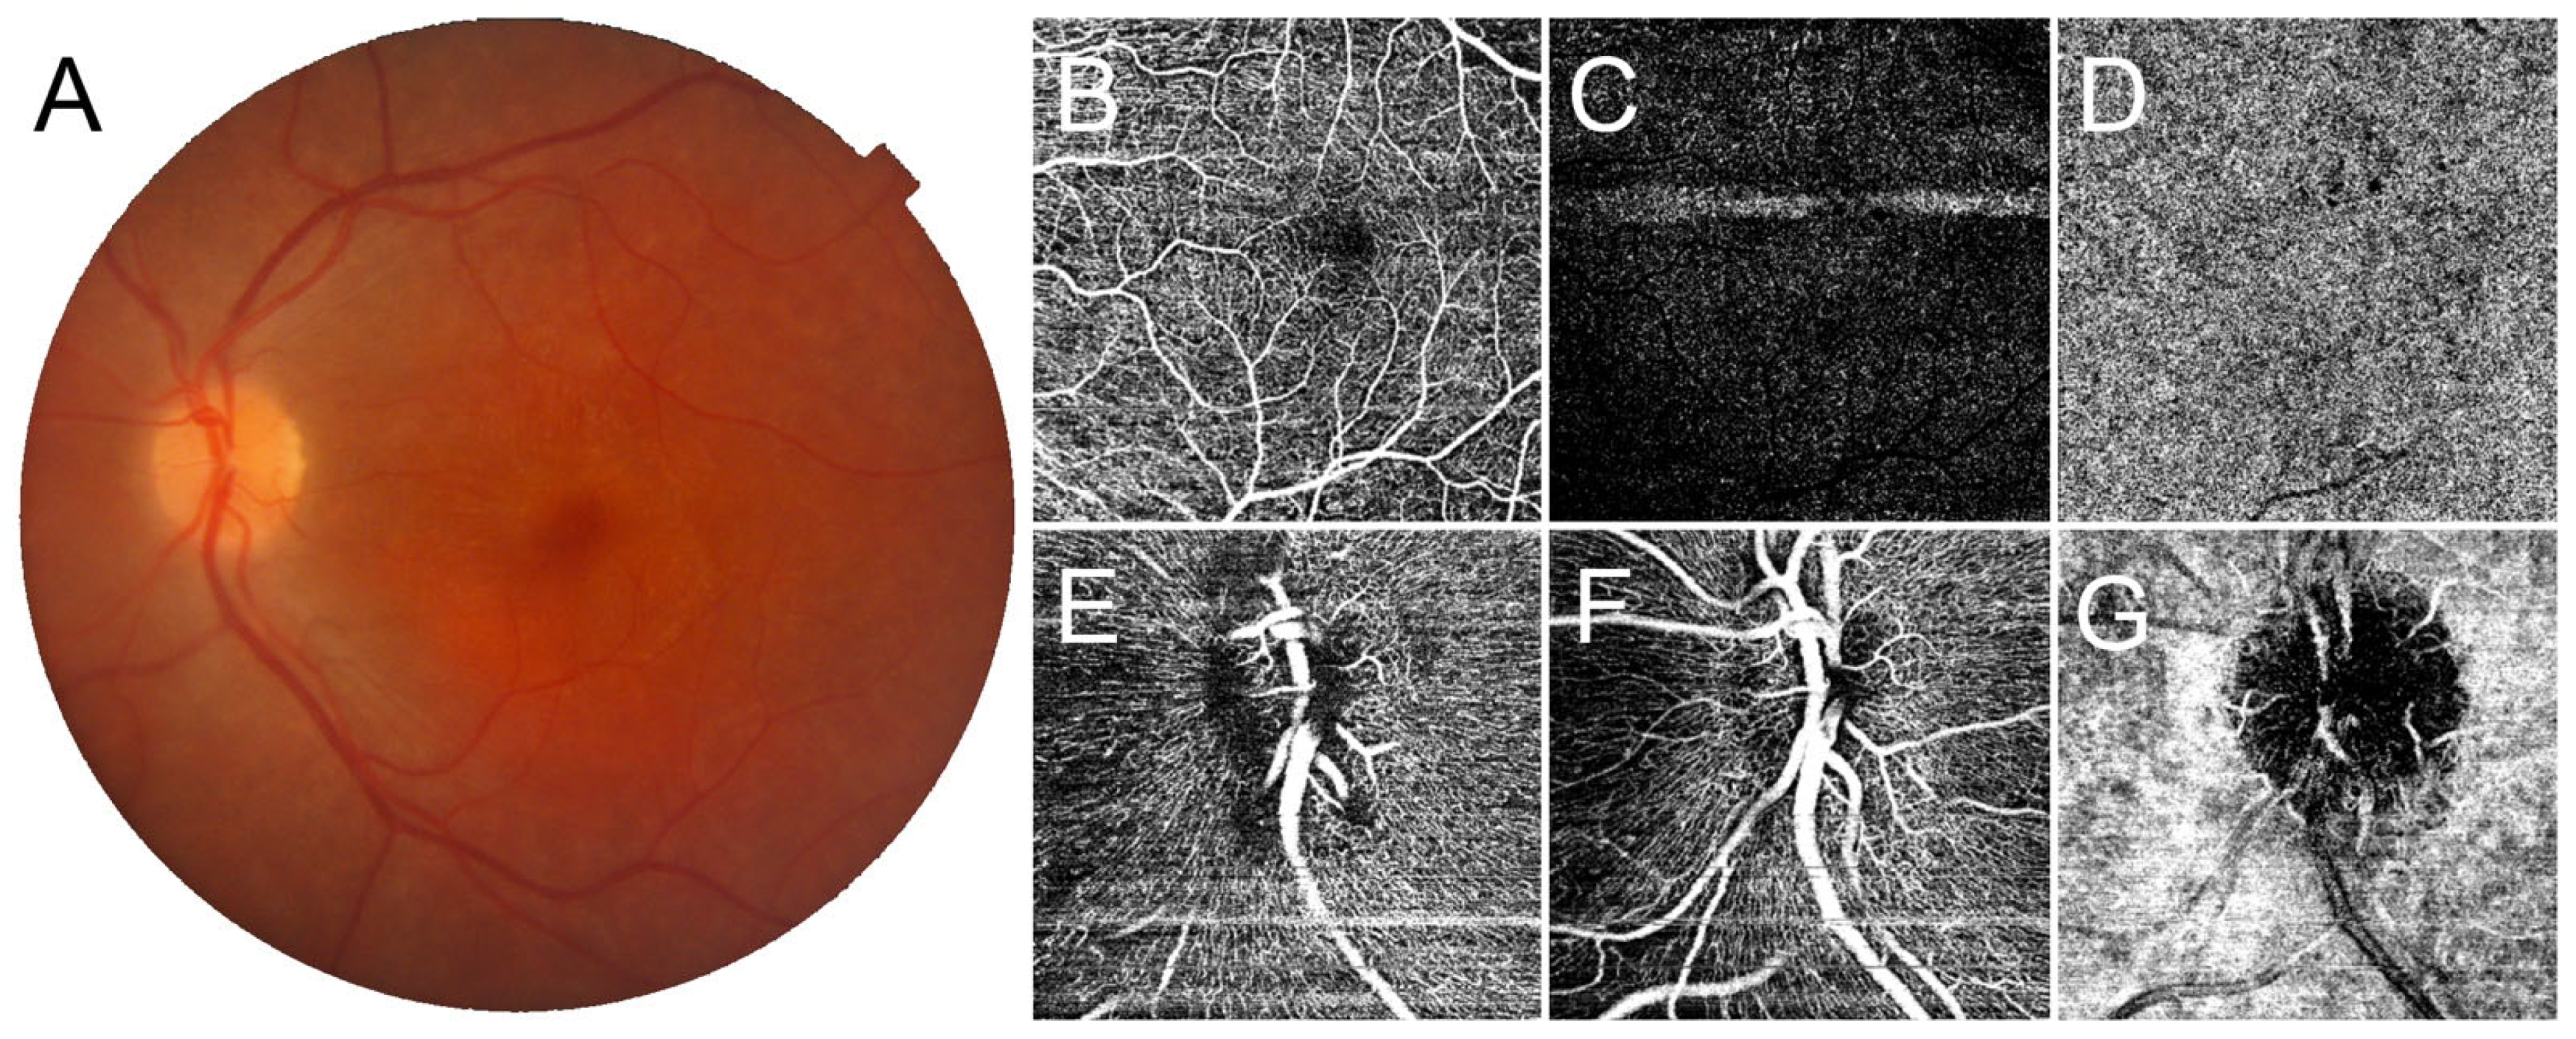

Figure 1.

Optical coherence tomography angiography (OCTA) findings in CRB1-associated retinal dystrophy presenting with macular atrophy. Color fundus photography (A) shows complete atrophy of the macular region. Here, OCTA detects a partially spared superficial capillary plexus (B), markedly disrupted deep capillary plexus (C), and completely absent choriocapillaris (D) in the macula. At the level of the optic nerve head, it is possible to observe a loss of the radial peripapillary capillary plexus (E), together with a rarefied superficial and deep capillary plexus (F), while the choriocapillaris appears preserved (G).